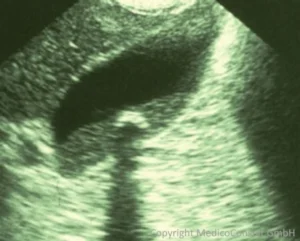

Sonographie

Die Sonographie hat eine Sensitivität von 95 % in Bezug auf Gallensteine in der Gallenblase (heller Reflex mit distaler Schallauslöschung bei Steinen ab 5 mm Größe), bei Choledocholithiasis (Steinen im Galleausführgang) sind die Steine erst dann gut sichtbar, wenn sie größer sind und/oder wenn ein Gallestau besteht.